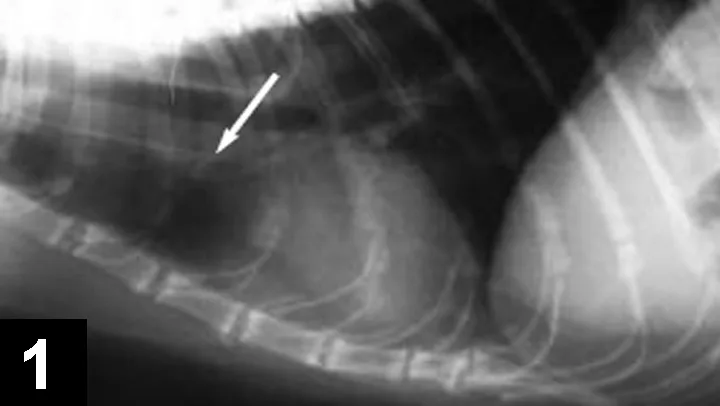

A radiograph shows a lateral view of a dog's abdomen, highlighting a significant opacity in the gastrointestinal tract indicated by an arrow. The image suggests the presence of a foreign body or mass, with the spine and ribs visible in the background.

Confirm catheter placement with a lateral thoracic radiograph (Figure 1. Lateral thoracic radiograph of jugular central venous catheter. Note that thedistal catheter tip (arrow) is located just outside of the right atrium).* Attach the 20-ml syringe directly to the female port of the 3-way stopcock.